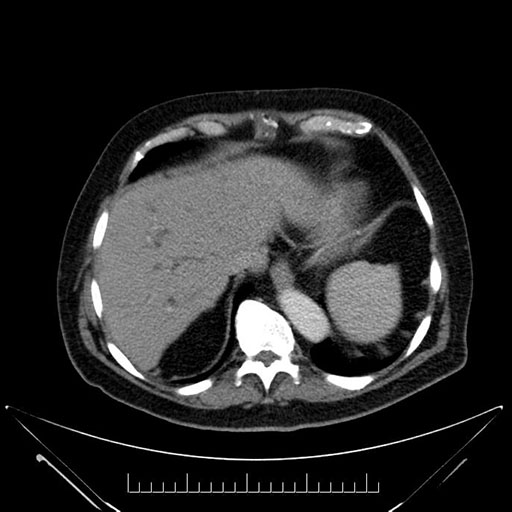

Whipple (pancreaticoduodenectomy) [case 7]

Imaging Analysis

Look through the patient's CT scan to identify any areas of concern for the necessary procedure.

Based on your CT findings, which issue(s) would give reason for "planned slowing down moment(s)" in this case?

Considering a standard Whipple procedure, what step(s) of the operation would you do differently in this case?